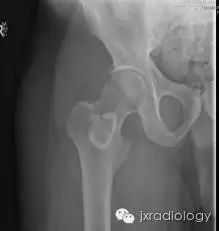

X线检查示骨纤维异常增殖症(Fibrous dysplasia ,FD)病变位于髓腔内,多见于骨干,病变区域多透亮,很少情况下出现高密度影(基质钙沉积时可出现),正常的骨小梁结构消失,代之以细颗粒“毛玻璃”样,有时病变周围的硬化骨带则可组成“果皮征”(rind sign)。

任何骨骼均有可能受累,但纤维异常增殖症多侵犯股骨(尤其是股骨颈)、胫骨、骨盆、肋骨、颅骨、头面骨及椎体。约 70%-80% 的患者为单处骨骼发病,而 20%-30% 患者为多处部位发病,其中两种较著名的多发纤维异常增殖症业已被报道(McCune-Albright 综合征和 Mazabraud 综合征)。